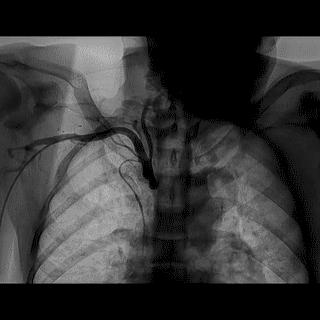

(4)LIMA桥血管造影

首选导管:JR4.0导管

其他导管:如果开口明显成角应选用专用的内乳动脉造影导管

➢ CASE 6

经股动脉途径TIG,非选择造影如果能清晰显影,可不做超选造影

➢ CASE 7

经左侧桡动脉途径JR4.0,非选择造影如果能清晰显影,可不做超选造影